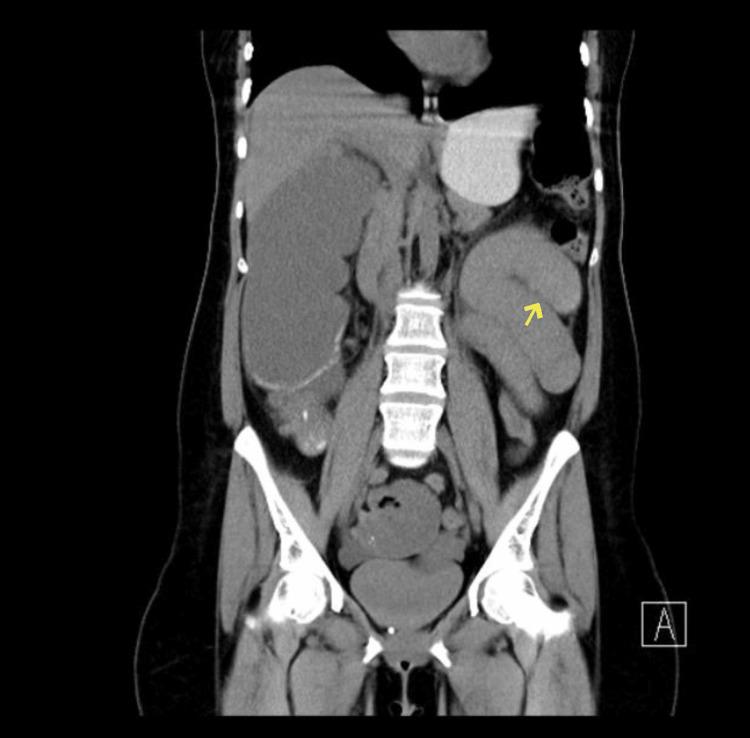

Multiple primary malignant tumors (MPMT) can be defined as more than two different tumors synchronously or metachronously forming in the same organ or different organs. The incidence of MPMTs varies dramatically between antemortem and postmortem examinations, becoming a serious medical issue. Evidence shows that the overall incidence of MPMTs is between 2.4% and 17%. Double primary malignancy (DPM) is considered the most common type of MPMT. In this case series, we present three cases of MPMT. The first case involved the colon and the breast, the second case involved the colon and the kidney, and the third case involved rectum and kidney.

多原发性恶性肿瘤(MPMT)可定义为在同一器官或不同器官中同步或异时形成的两种以上不同肿瘤。MPMT的发病率在生前检查和死后检查之间差异很大,成为一个严重的医学问题。证据表明,MPMT的总体发病率在2.4%至17%之间。双原发性恶性肿瘤(DPM)被认为是MPMT最常见的类型。在本病例系列中,我们呈现了3例MPMT病例。第一例涉及结肠和乳腺,第二例涉及结肠和肾脏,第三例涉及直肠和肾脏。